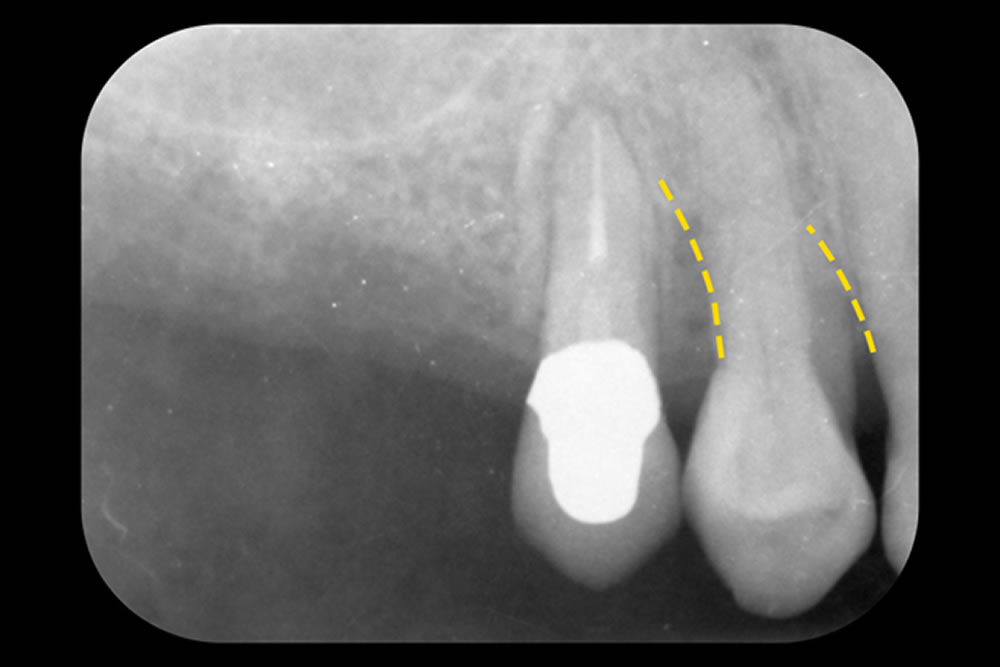

- 3.1 重症化した歯周病を手術なしで治療した症例

- 3.2 グラグラする歯を手術なしで治療した症例

- 3.3 他院で抜歯と診断された歯を手術なしで治療した症例

- 3.4 骨を部分的に欠損した歯を手術なしで改善した症例

まずは、論より証拠。日本歯周病学会専門医である当院の院長が実際に行った「重度歯周病で抜くことになる確率が高い歯を抜かなかった歯周病改善例」をご紹介します。

初診時(上写真)、右下6番目の歯は今にも抜け落ちそうな状態でしたが、重度歯周病治療【MINST】によって、症状を改善し、術後1年後(下写真)には歯周組織もしっかりと再生しました。

※外科処置なし・再生材料も使用しておりません。